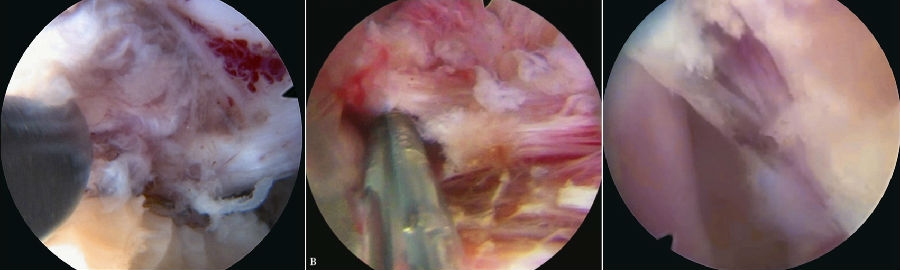

5. 黄韧带扩孔,直视镜下沿黄韧带裂隙将锥形工作套管轻柔地旋转入椎管,可见破碎的髓核组织及纤维环组织。(图30~图35)

6. 确定髓核组织后,用镜下髓核钳将突出髓核组织切除(图36~图40),直至清晰地看到后纵韧带和神经根周围脂肪组织。

7. 双极射频刀头电极在直视下行残存髓核组织消融止血,纤维环破口皱缩成形。(图41)

8. 减压充分的标志是可在镜下看到神经根及硬膜囊随呼吸波动(图42),仔细探查无脱出髓核残留后,退出内镜系统,伤口缝合

图31-图34 篮钳咬除硬膜表面黄韧带;篮钳咬除黄韧带并注意隆起的硬膜囊;

剥离子插入突出髓核并开始旋转工作套管;

继续旋转工作套管,借助套管头端将神经从髓核表面移开

图35-图38 下行根和硬膜囊已经从髓核表面移开;髓核摘除,白色为突出髓核;

髓核摘除过程中;髓核被拖出过程中

图39-图40 大块髓核被拖出;大块髓核被清除过程中

图41-图42 双极射频止血,纤维环成形;髓核摘除后硬膜囊和下行根减压松解